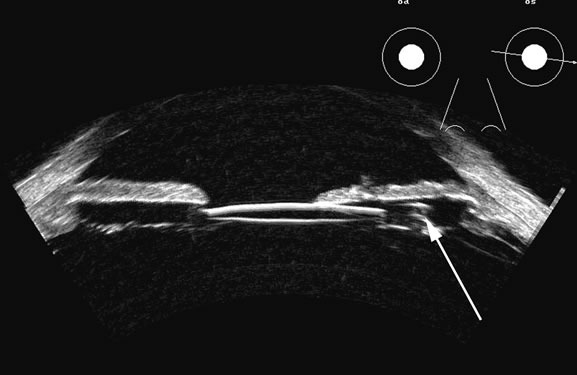

Fig. 4. A clinically well-placed posterior chamber intraocular lens nevertheless had patient complaints of photophobia and irritation due to a folded haptic (arrow).

Fig. 5. An anterior chamber intraocular lens has had the support haptics dislocate posterior to the iris plane and can be seen as typical foreign body echogenic reflections (arrows).